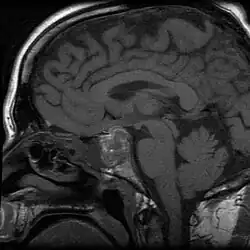

![]() Udar przysadki, w przebiegu którego wystąpiły bóle głowy i utrata wzroku u 43-letniego mężczyzny. W centrum obrazu RM w sekwencji T1 widoczna jest masa przemieszczająca skrzyżowanie wzrokowe | |

Udar przysadki – choroba ośrodkowego układu nerwowego polegająca na zawale lub krwawieniu do przysadki mózgowej, często związanymi z obecnym gruczolakiem przysadki[1][2][3][4][5].

Przez pierwszy tydzień od wystąpienia udar daje izointensywny sygnał w sekwencji T1-zależnych oraz hipointensywny w T2-zależnych; wystąpienie pogrubienia błony śluzowej zatoki klinowej w ciągu kilku pierwszych godzin sugeruje rozpoznanie choroby[6]. Od 7 dnia dochodzi do zwiększania intensywności sygnału przysadki w obrazach T1-zależnych, a w czasie kolejnego tygodnia w obu sekwencjach[6].